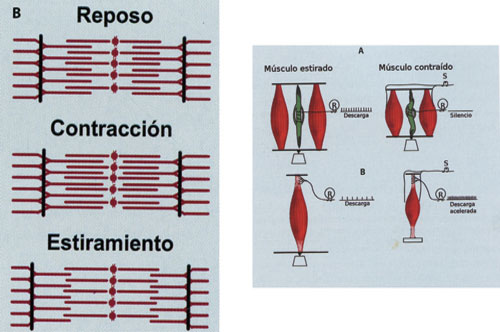

Sabemos por fisiología , que cuando un estímulo eléctrico es aplicado a un músculo acortado en su longitud es decir, con sus sarcómeros contraídos, la capacidad de contracción ante el estímulo se encuentra disminuida en un 60%.

Por el contrario , si el músculo es elongado en su longitud, es decir con sus sarcómeros estirados, la tensión de contracción es enorme.

que conlleva al estímulo de los husos neuromusculares por estiramiento, lo

que no permite el estado de reposo muscular necesario a los músculos de la masticación.

DIBUJO I

DIBUJO II